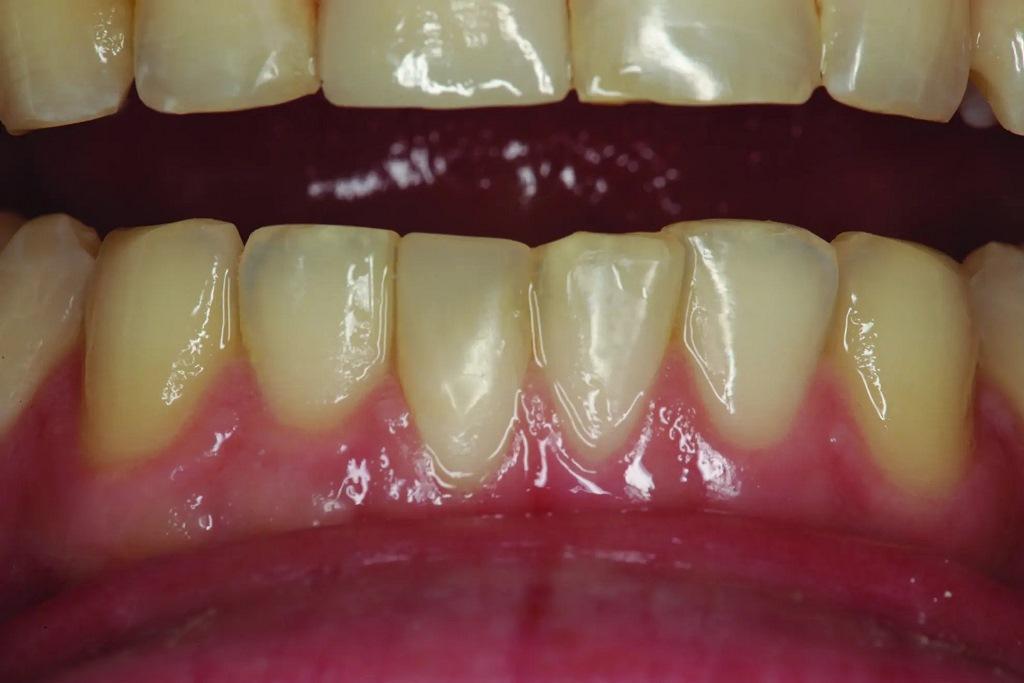

А как насчет выравнивания зубов-антагонистов? На режущих краях зубов 31 и 41 (фото 2) наблюдался чрезмерный износ. Со стороны резцов был виден значительный износ всех краев нижней челюсти из-за окклюзионного заболевания, которое часто наблюдается, но не лечится (фото 3). Также зуб 41 располагался на лицевой стороне таким образом, что при выступающей экскурсии он преждевременно соприкасался с небной поверхностью зуба 11, создавая дополнительную нагрузку как на небную поверхность, так и на резцовый край зуба 11, прежде чем соединиться с остальной частью переднего сегмента верхней челюсти. Это демонстрирует, что решение этих проблем реставрационными методами включает в себя нечто большее, чем просто исправление сколов композитной реставрации.

Фото 3: Резцовый вид показывает, что зуб 41 был наиболее расположенным к лицу резцом нижней челюсти в форме дуги.